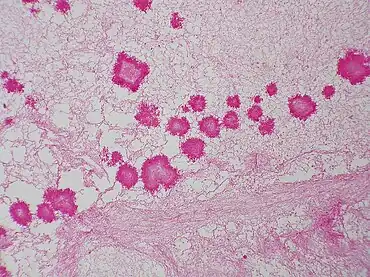

Geotrichum candidum belongs to the Ascomycota division and typically forms white, flat, suede-like colonies. Microscopically, it produces hyaline, septate hyphae that fragment into chains of arthroconidia—its asexual spores.G. candidum is also an opportunistic pathogen[20]

Geotrichum candidum culture -